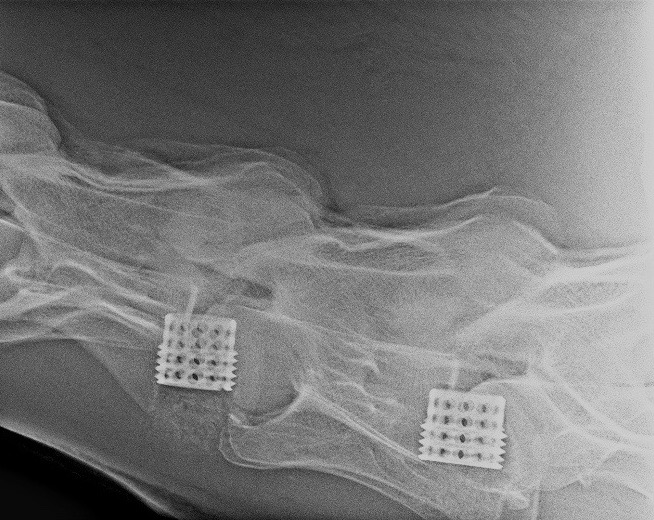

Pokud neurologické vyšetření potvrdí ataxii (stupeň 1–5), je potřeba stanovit její přesnou příčinu. Nejčastěji se jedná o zúžení páteřního kanálu v oblasti krčních obratlů, kde pak dochází k útlaku míchy – Wobblerovu syndromu. Existují ale i další příčiny ataxie, které je potřeba vzít na vědomí, například vrozené abnormality krčních obratlů (vertebrální malformace), úrazy krční páteře, nádory, virové infekce (EHV), bakteriální infekce (abscesy, záněty meziobratlových plotének a kostí) (obr. 2a, b, c), parazitární infekce nebo některé toxiny.

Obrázek 2a, b: Hříbě s ataxií a horečkou způsobenou zánětem kostí obratlů C6–C7. Na CT je jasně patrné výrazné poškození kostí v důsledku infekce (bílé šipky). Na obrázku 2b je stejný případ z jiného pohledu